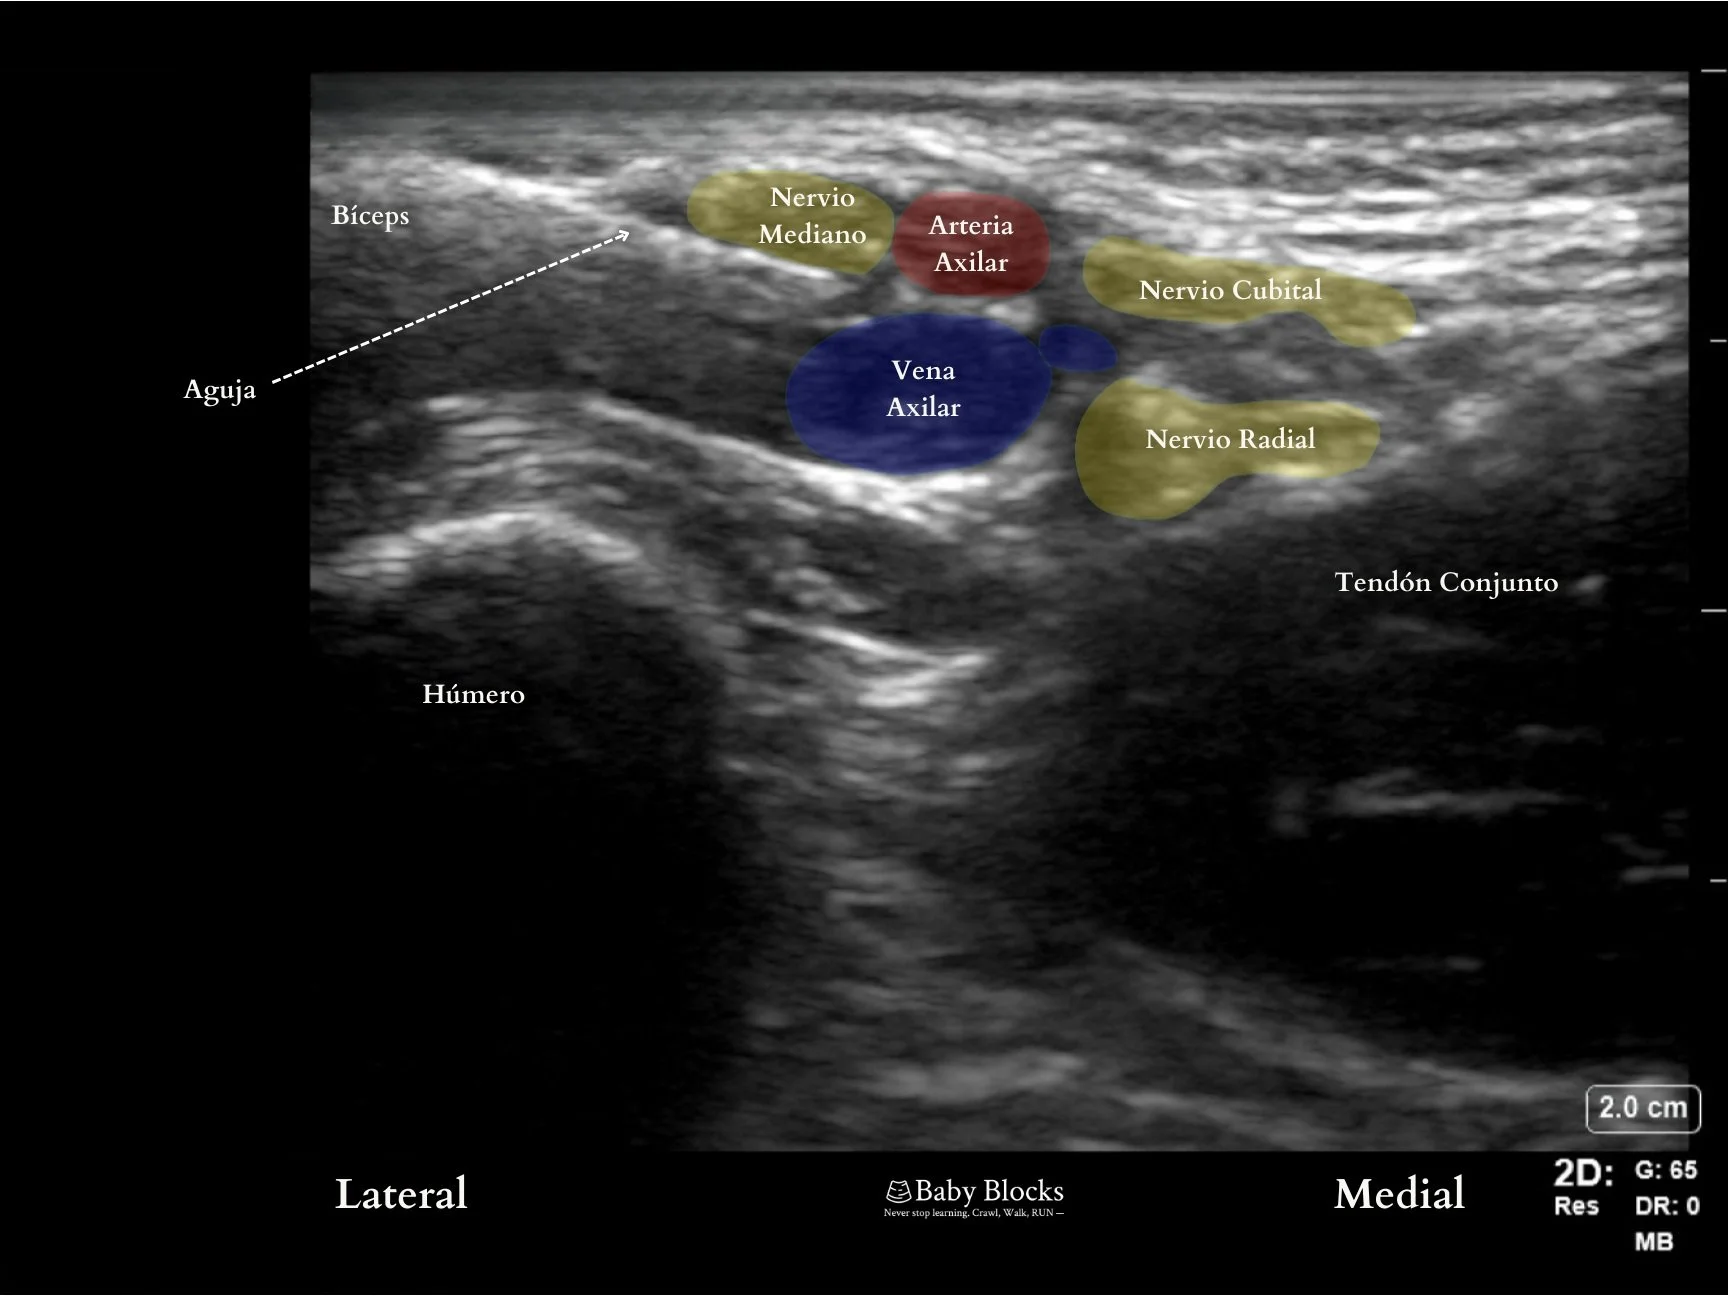

El transductor puede colocarse superior a la fosa axilar, quedando perpendicular a los pliegues axilares. Se identifica la arteria axilar en corte transversal y alrededor de ella se visualizan los nervios (mediano, radial y cubital), junto con múltiples venas axilares. Es importante recordar, que resulta muy común encontrar variaciones anatómicas tanto en la ubicación de los nervios, como en el número de venas.

Durante el abordaje, introduzca la aguja en plano, en una dirección de lateral a medial a lo largo del miembro superior. El objetivo principal será la inyección del anestésico local en la vaina neurovascular que contiene los nervios mediano, radial y cubital, en la región axilar, entre la arteria axilar y el tendón conjunto. Esto se puede lograr tanto administrando el anestésico local periarterial como rodeando cada nervio de manera individual con el anestésico local. Se han descrito múltiples localizaciones para la inyección periarterial que ofrecen una eficacia similar.

Imágenes de Ultrasonido del Bloqueo Axilar